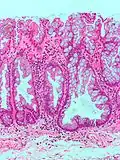

| Тип полипа | Гистологическое строение | Риск злокачественного развития | Микроснимок[3] | Синдром |

| Гиперпластический полип | Зазубренные неветвистые крипты | Нет | ![]() |

Синдром гиперпластического полипоза (множественные полипы) |